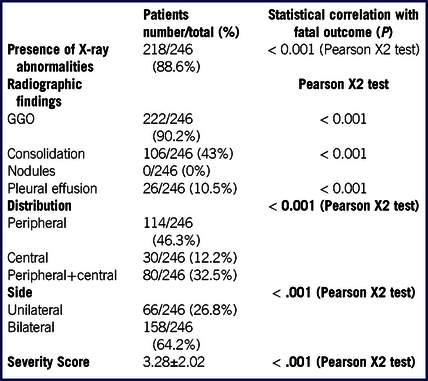

One hundred fifty-six of 246 (63%) CXR were executed in the posteroanterior projection on a portable X-Ray unit. Two hundred eighteen of 246 (88.6%) of CXR showed abnormalities. Most patients (222/246; 90.2%) showed GGO, with bilateral (158/246, 64.2%) and peripheral (114/246, 46.3%) distribution. The mean radiographic severity score was 3 ± 2. Interobserver agreement was excellent (Cohen’s K coefficient: 0.901). Overall imaging findings are listed in Table 4.

TABLE 4 Radiographic Findings and Their Distribution, and Radiographic Severity Score in Our Patient Population and Correlation With the Fatal Outcome

Abbreviation: GGO, ground glass opacity.

The correlation upon univariate analysis of the analyzed variables with fatal outcome is listed in Tables 1, 2, 4.

At CXR, GGO with peripheral distribution, consolidation, pleural effusion, and the severity score showed a significant correlation with fatal outcome (P < 0.001).